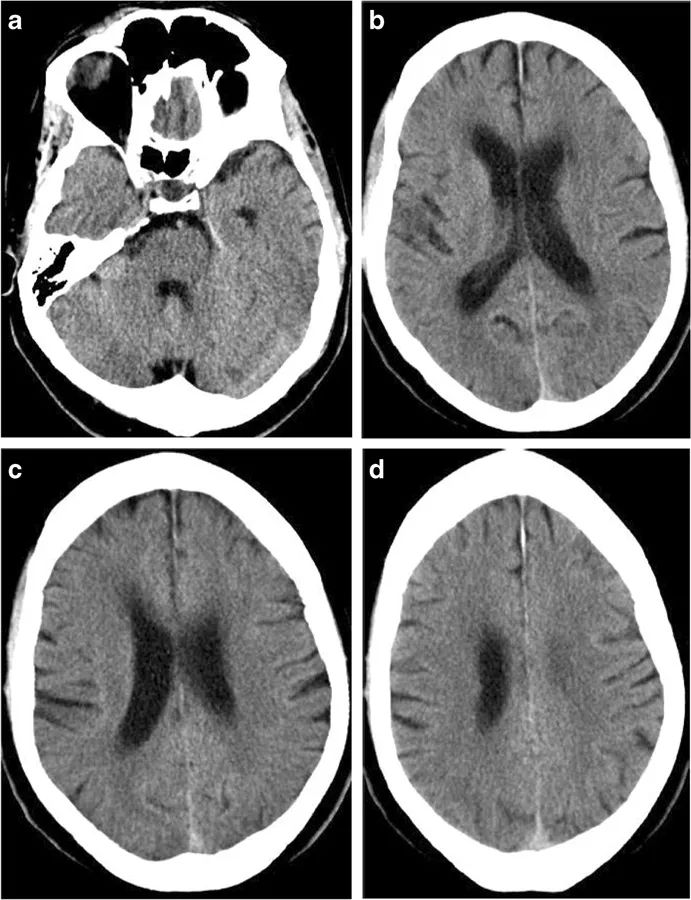

图1 62岁男性,突发左侧偏瘫87分钟后完成了CT扫描,但CT上并未检测出患者的细胞毒性脑水肿,小脑半球上两个微小的病变并不能对症状做出解释(a~d)。症状发作后3小时10分钟,患者完成了MRI扫描,DWI显示患者大脑和小脑半球显现出多发栓塞情势的小病灶,大脑半球右侧为著,这解释了患者的卒中症状(f~h)。经进一步检查,本例患者有主动脉夹层。